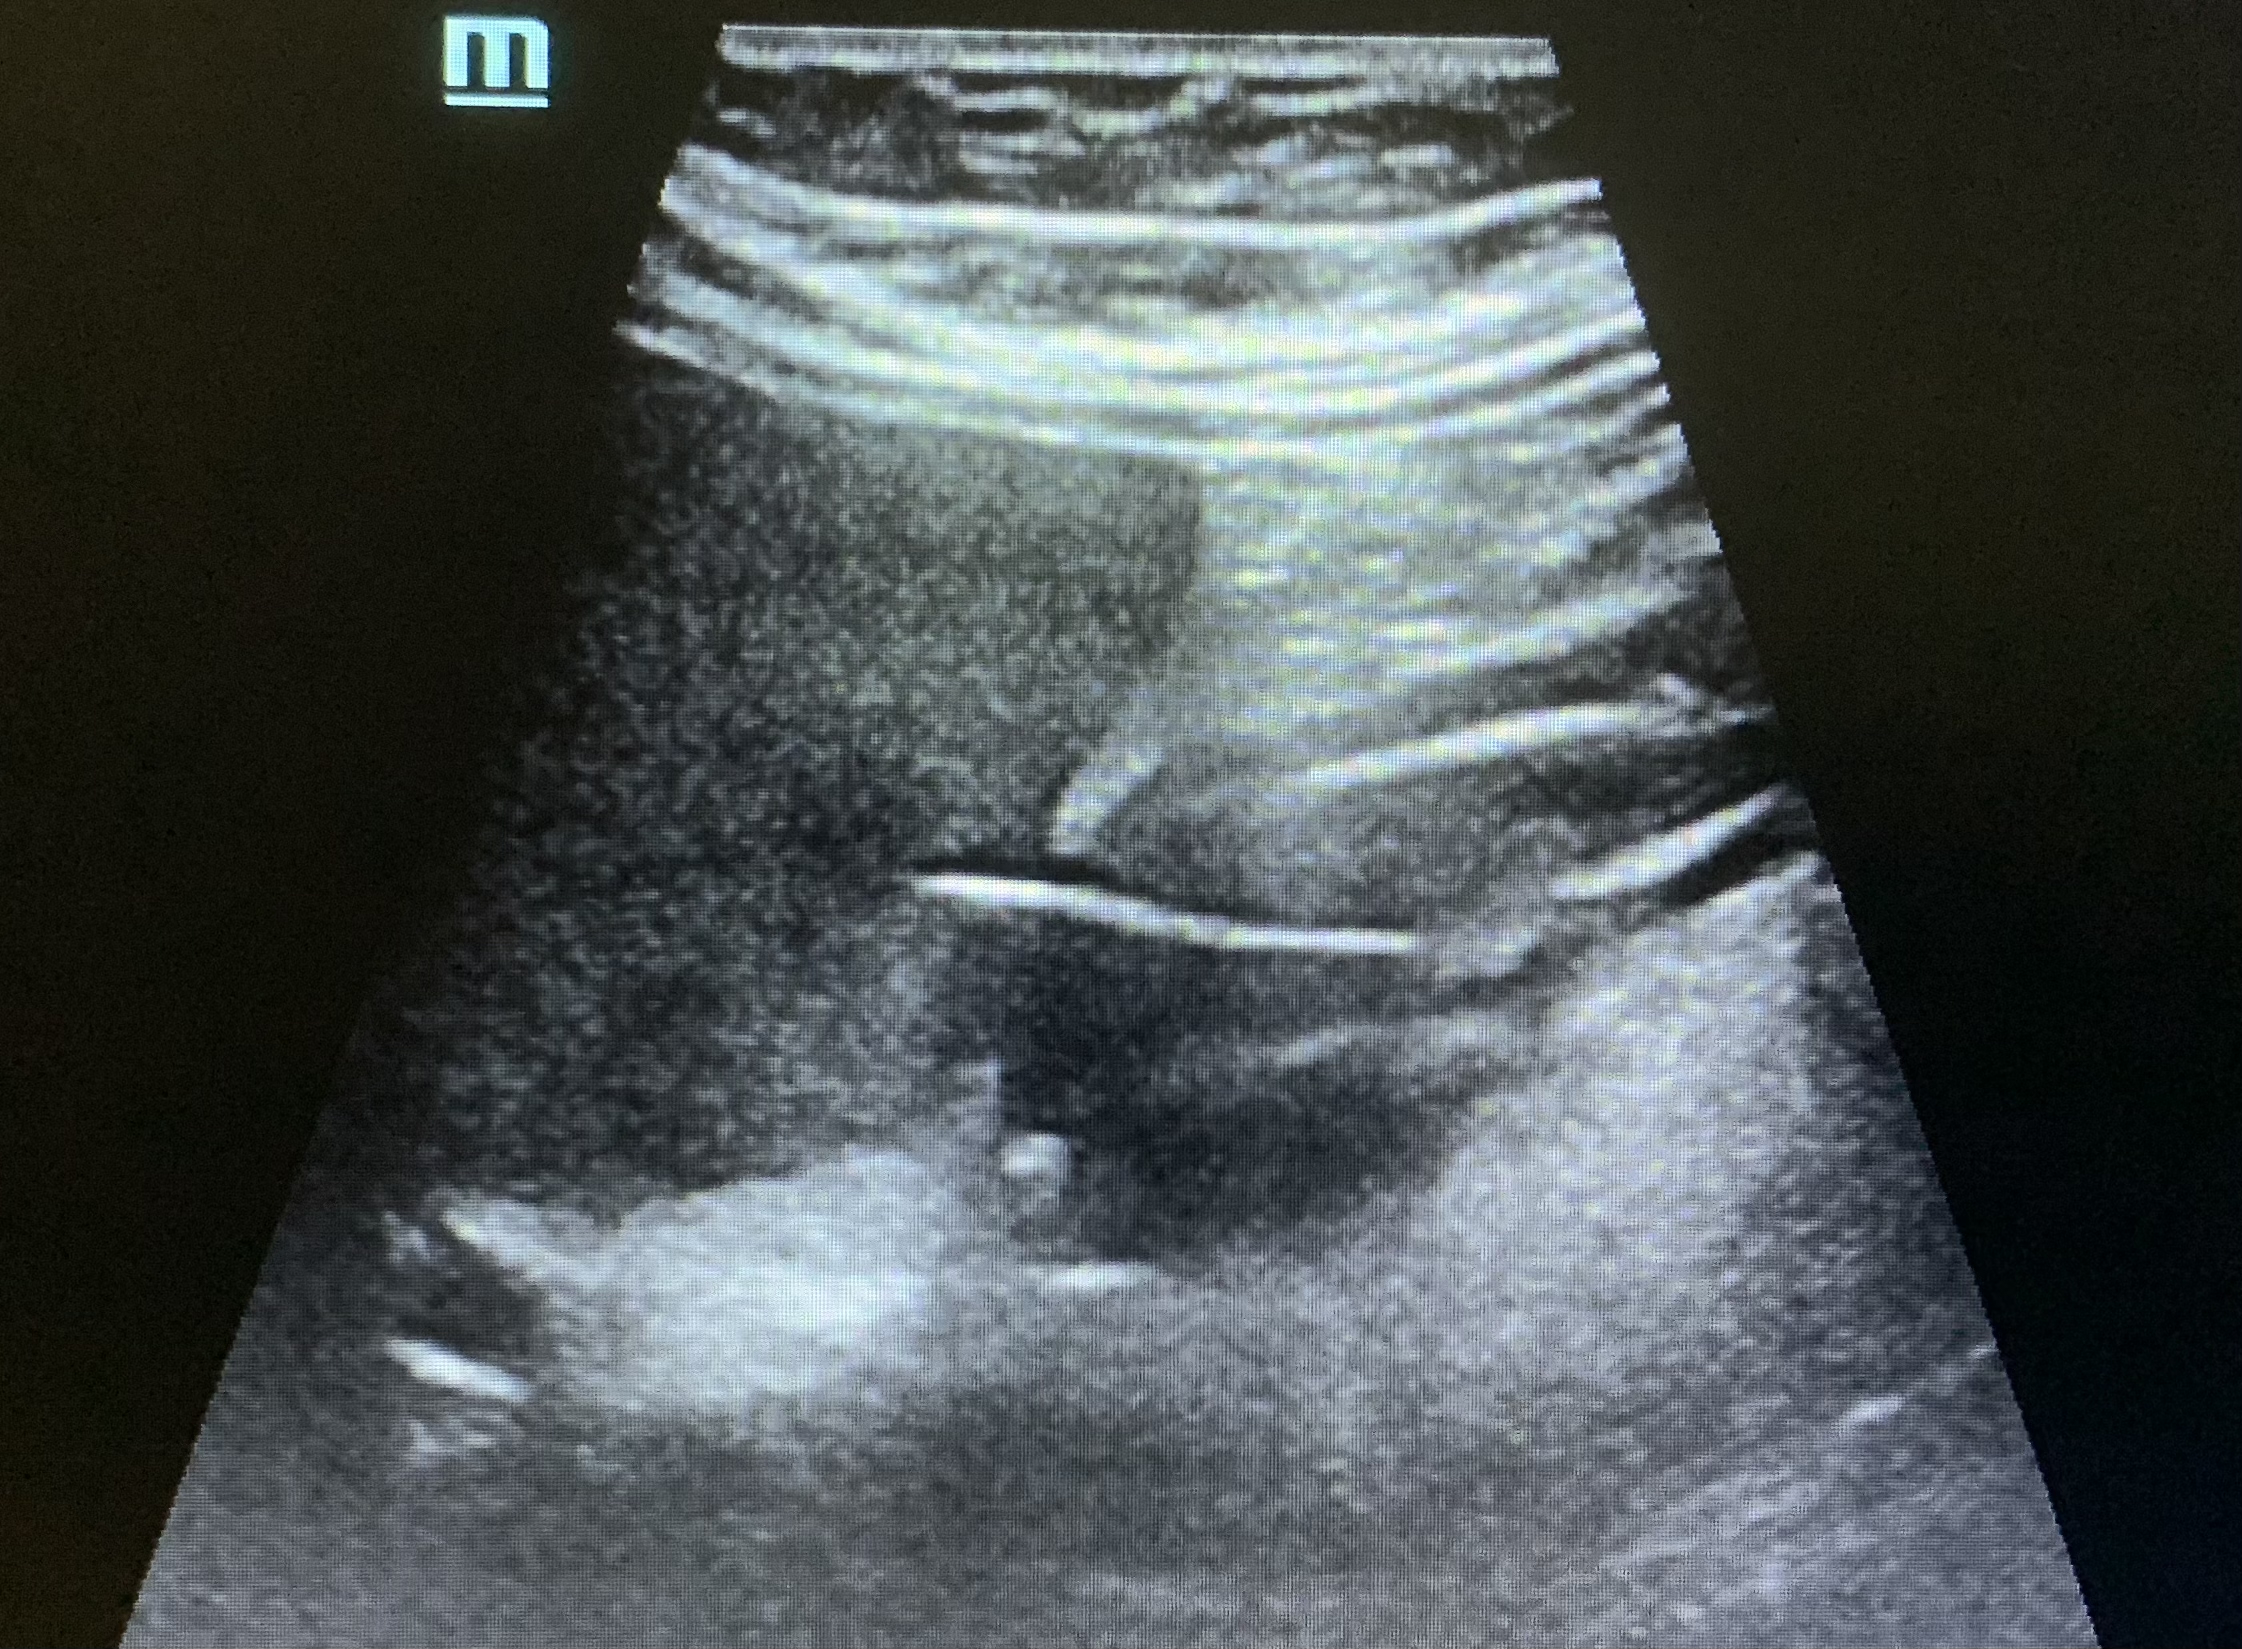

这里是清华长庚超声科

被诊断为可疑胃癌的患者

不肯接受命运的审判

北上求医

张华斌主任、谭庆亭医师反复检查

探头下的黑白世界里

“一根刺”终露真身

最终判定出竹签刺穿胃壁进入肝脏的罕见病例

“我第一次,见到了送给自己的匾”

这是认真换来的价值

更换来了一个生命的新春